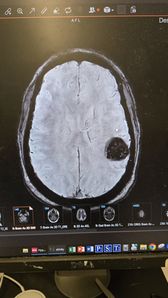

I care about justice for the less fortunate. I have a brain tumor and im trying to raise money to survive the cost of recovery without becoming homeless.